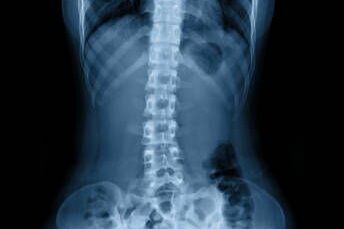

ปวดหลังส่วนล่าง สลักเพชรจม

นิ้วล็อค ปวดข้อมือ กระดูกคดจากท่าทาง

หมอนรองกระดูกทับเส้นประสาท

กระดูกคอ/หลังเสื่อม